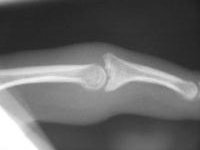

PIP is swollen and a bit tender. E/F 20/80, probably a few degrees of radial angulation.

Range of motion not terrible, but...